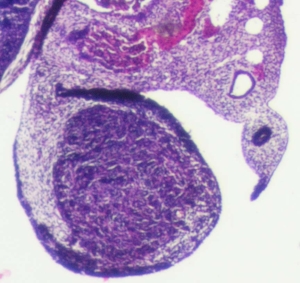

Stage 21

CfS 21

d37-39